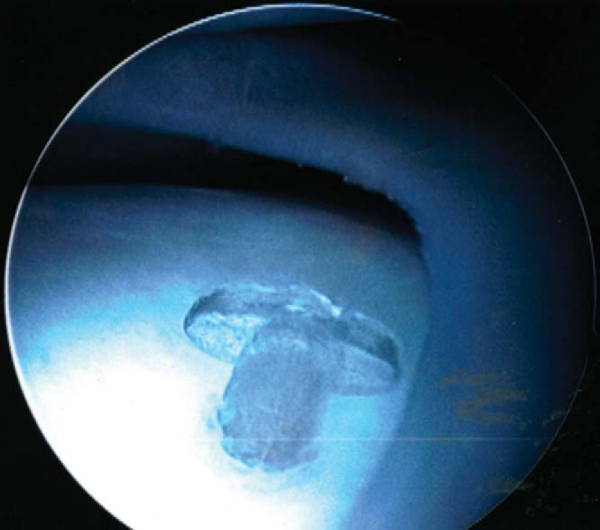

Complications reported with these devices, especially the arrow, have included transient synovitis, inflammatory reaction, migration of devices, chondral damage, cyst formation, and device failure (

Fig. 46-5

). [2] [7] [14] [19] [21] [22] [24] [25] [26] A study with a 2-year minimum followup had a clinical failure rate of only 7% but had a local soft tissue complication rate of 31.6% with two devices that migrated through the skin.[15]

Figure 46-5 |